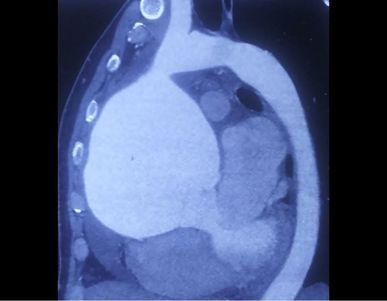

Nagpur News सलग ८ तासाच्या शस्त्रक्रियेनंतर एका ३५ वर्षीय व्यक्तीच्या हृदयातून १२.७५ से.मी. आकाराची गाठ काढून शहरातील डॉक्टरांनी या रुग्णाला नवे जीवन दिले.

नागपूर : सलग ८ तासाच्या शस्त्रक्रियेनंतर एका ३५ वर्षीय व्यक्तीच्या हृदयातून १२.७५ से.मी. आकाराची गाठ काढून शहरातील डॉक्टरांनी या रुग्णाला नवे जीवन दिले. मंगळवारी झालेल्या या जोखमीच्या शस्त्रक्रियेमुळे केवळ वैद्यकीय क्षेत्राचेच नव्हे, तर नागपूरचेही नाव उंचावले.

मध्य प्रदेशातील सौंसर येथील ३५ वर्षीय रुग्णाच्या हृदयात गाठ असल्याने त्याला नीट श्वास घेता येत नव्हते. झोपताही येत नव्हते. अत्यंत गंभीर स्थितीत हा रुग्ण कार्डियो वस्कूलर सर्जन डॉ. सौरभ वार्षणे यांच्याकडे दाखल झाला. अशा स्थितीत तो आतापर्यंत कसा जिवंत राहिला, याचेच डॉक्टरांना आश्चर्य वाटले. रुग्णाच्या या आजाराला वैद्यकीय भाषेत ‘एनयुरिज्म’ म्हटले जाते. या रुग्णावर ‘बेंटल सर्जरी’ करण्यात आली.

जगाच्या इतिहासात आतापर्यंत सर्वात मोठी १४ से.मी. गाठ काढल्याची नोंद आहे. मंगळवारी शहरात झालेली ही शस्त्रक्रिया अलीकडच्या काळात सर्वात मोठी शस्त्रक्रिया आहे. याला ज्येष्ठ हृदयरोग शल्यचिकित्सक डॉ. पी. के. देशपांडे यांनीही दुजोरा दिला. ही शस्त्रक्रिया डॉ. वार्षणे यांच्या नेतृत्वात, बधिरीकरण तज्ज्ञ डॉ. श्रीकांत बोबडे, हृदयविकार तज्ज्ञ गिरीश गौतम, डॉ. दर्शनी सोनी, परिचारिका राणी शेख व ब्रदर जफ्फार खान आदींनी यशस्वी केली.